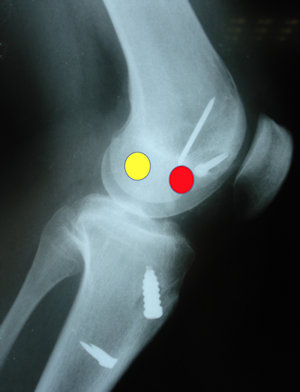

Bu nedenler arasında en sık görülen sorun ilk cerrahi sırasında yapılan teknik hatalardır (Resim 1). Bunlar arasında tanı sorunları, tünel yerleşimi, tespit materyalleri, eşlik eden menisküs ve kıkırdak yaralanmalarının uygun olmayan tedavisi gibi sorunlar en önemli yeri tutar.